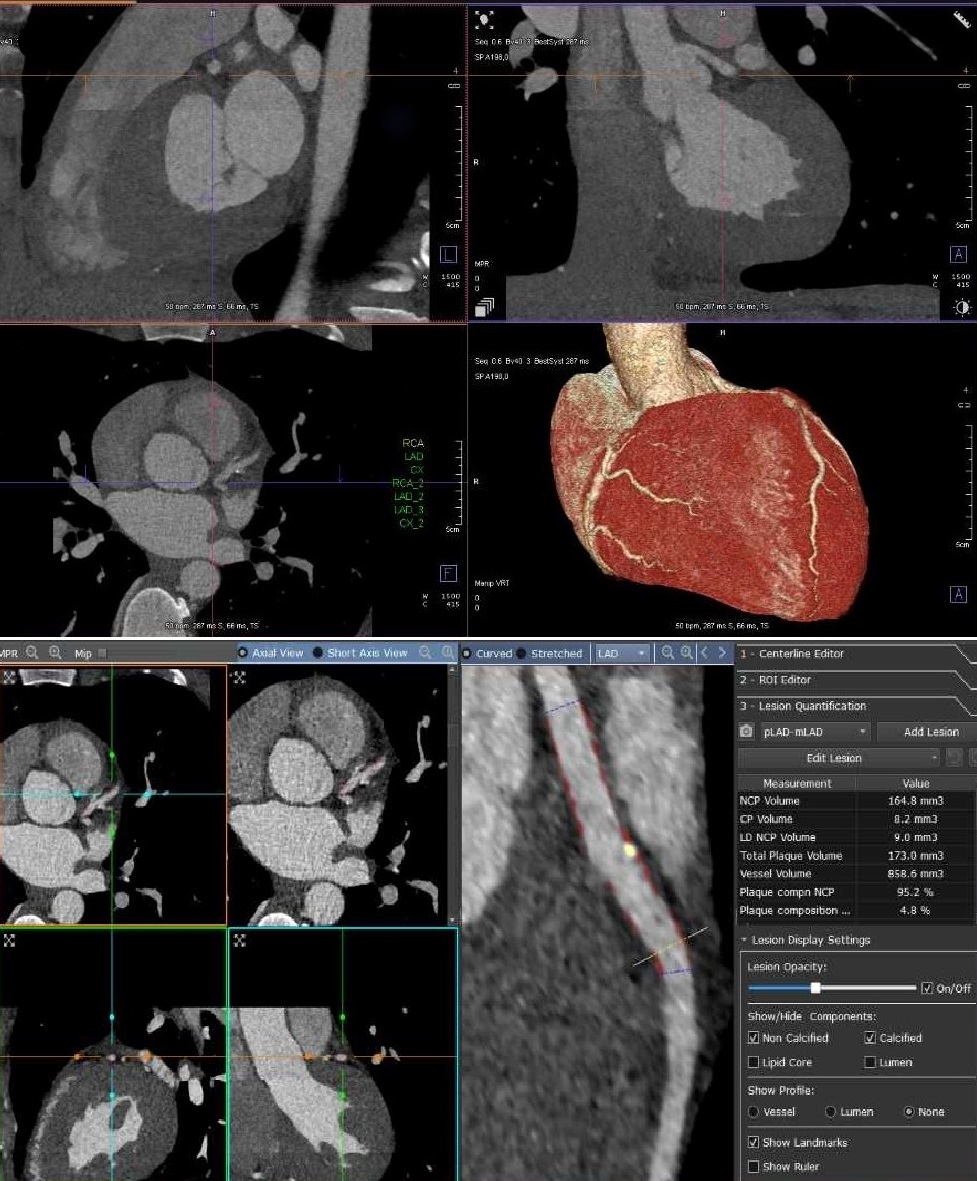

Excited about the next 3 months at the Dey Research Lab (Cedars-Sinai Biomedical Imaging Research Institute) with director Damini Dey as my mentor. Will be continuing my work on investigating coronary disease with AutoPlaque. Now also using artificial intelligence.🫀🧠 Danish Cardiovascular Academy Research Unit of Cardiology, OUH

Teaching and preparing our team for AutoPlaque analyses of the numerous CTAs in our exciting national multicenter projects #INTENCT and #DANCODE leaded by Axel Diederichsen. 🫀 Thank you Damini Dey for making this possible! Danish Cardiovascular Academy Research Unit of Cardiology, OUH